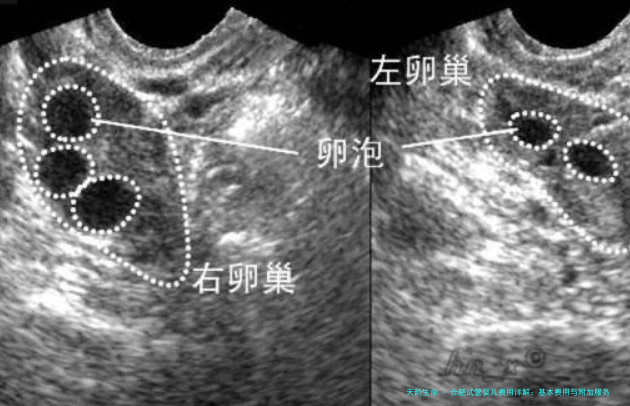

促排是试管婴儿过程当中特别主要的1个环节,通过注射诱导排卵药物来刺激卵巢出现多个卵子。药物的抉择和用量会根据病人的各别差别而有所差异。一般来说,促卵泡生成药物费用较高,可能在1万元至三万块之间。